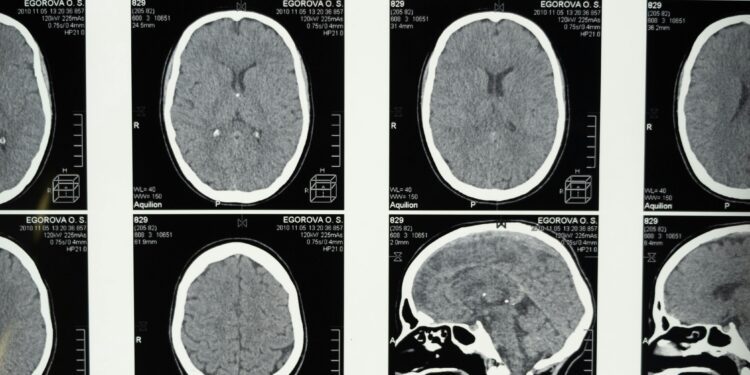

Biomarker development is compressing the timeline between pathology and detection. Blood‑based amyloid and tau assays, neurofilament light chain measurements, and inflammatory markers are increasingly studied as early risk indicators, with validation papers appearing in major journals and summarized in research updates from agencies such as the National Institutes of Health at https://www.nih.gov. Earlier detection improves prognostic precision and raises ethical and financial questions simultaneously. Risk knowledge without definitive intervention creates clinical ambiguity.